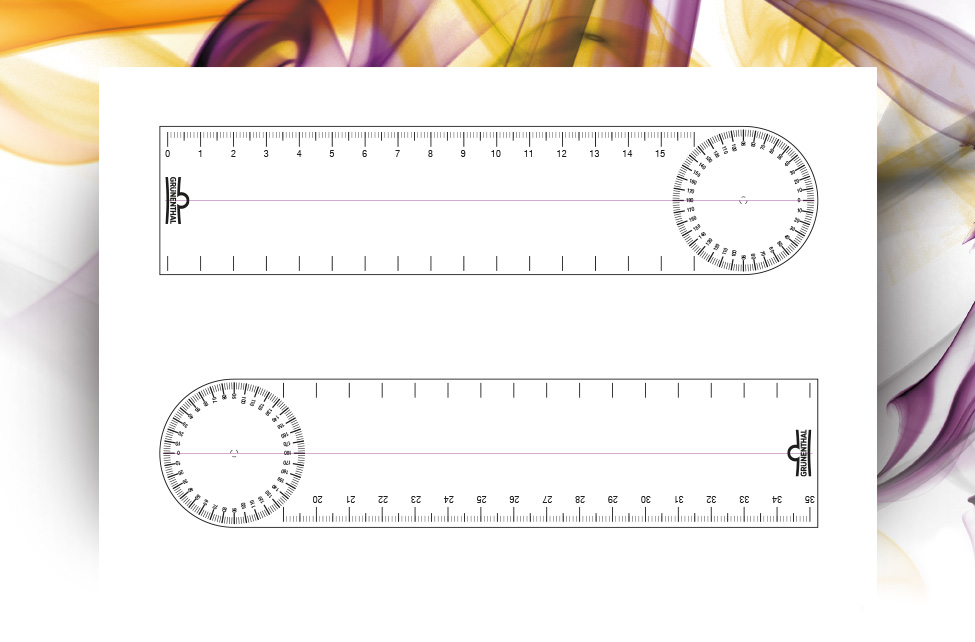

Repositorio de recursos

Guías de abordaje terapéutico, ejercicios para pacientes y herramientas que le ayudarán en su diagnóstico.